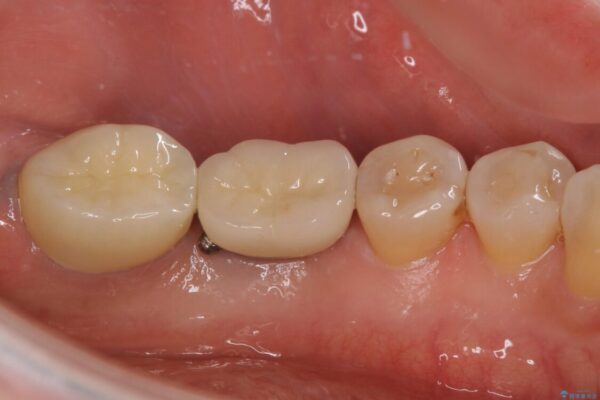

治療後

• しみる奥歯 オールセラミッククラウンによる補綴治療 治療後画像